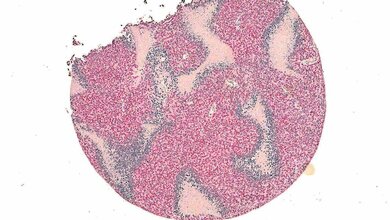

Doch auch bei der Diagnostik geht es mit Riesenschritten voran. Neben den neuen Möglichkeiten in der Bildgebung ist hier beispielsweise Liquid Biopsy ein Schlagwort. Die Nukleinsäureanalytik zum Nachweis von Tumorzellen und Tumor-DNA sorgt für Furore.